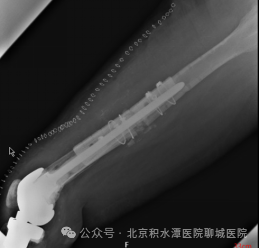

下肢X线片

翻修术后X线片